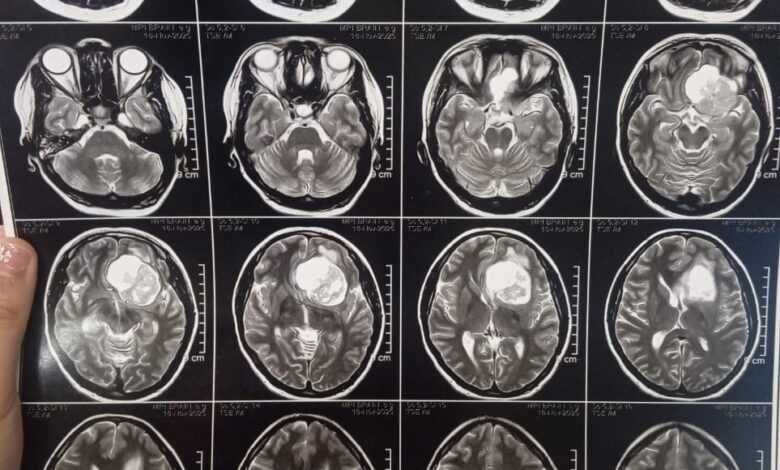

ومن جانبه، أوضح الدكتور مجدي القاضي عميد كلية الطب البشري ورئيس مجلس إدارة المستشفيات الجامعية أن المريضة حضرت وهي تعاني من صداع شديد وارتفاع بضغط المخ مع تدهور ملحوظ في حدة الإبصار، وبإجراء الفحوصات الطبية اللازمة وأشعة الرنين المغناطيسي، تبيّن وجود ورم كبير بقاع الجمجمة ضاغط على أعصاب البصر والأوعية الدموية المغذية للمخ، ما استدعى التدخل الجراحي العاجل باستخدام أحدث التقنيات الدقيقة.